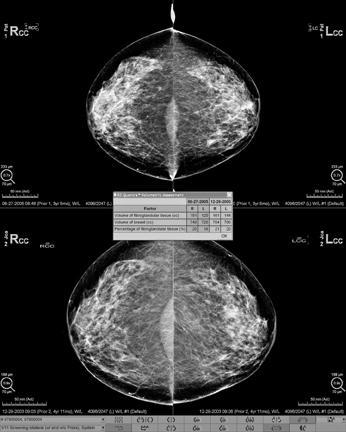

Commercial software for volumetric breast density evaluation is now available, including Volpara from Matakina and iCAD (for GE and Hologic digital mammogram systems, the system used in the author’s practice) and Quantra from Hologic (for Hologic digital mammogram systems).

Future Direction

Additional studies will need to be performed to determine whether automated, volumetric breast density assessments predict cancer risk better than subjective visual assessments. With a quantitative, standardized way of reporting breast density, there is now no reason not to incorporate density data into the numerous models that calculate breast cancer risk, especially since breast density is one of the strongest independent risk factors for cancer.